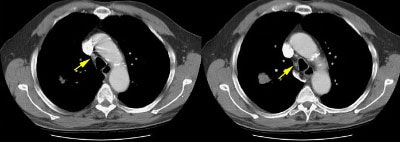

Example of the normal hilar interstitium: The images below are from a patient without bronchogenic carcinoma. The images demonstrate normal hilar lymphatic tissue (yellow arrow right image) which appears as a low density region between the bronchus and pulmonary vessel. A small calcified node is seen on the right (red arrow) in this patient with prior granulomatous disease. NOTE: Click image to enlarge.